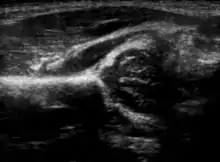

Hip dysplasia diagnosed by ultrasound[40] and projectional radiography ("X-ray").[41] Ultrasound imaging is generally preferred at up to 4 months due to limited ossification of the skeleton.[39][notes 1]